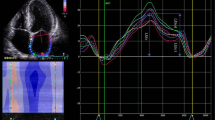

The intra- and inter-observer agreements of LASr, LAScd, and LASct are summarized in Table 4 and Fig. 5.

Bland-Altman analysis for intra- and inter-observer variabilities for LA strain measurements. a, b, c Intra-variabilities of LASr, LAScd, and LASct, respectively. d, e, f Inter-variabilities of LASr, LAScd, and LASct, respectively. LAScd = left atrial conduit strain; LASct = left atrial contraction strain; LASr = left atrial reservoir strain